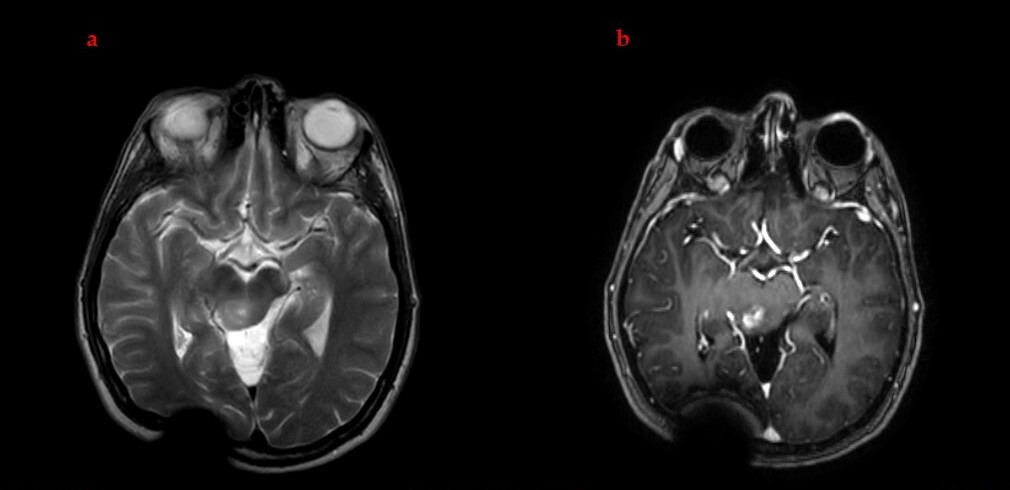

2.6. Treatment Response and Clinical Outcome